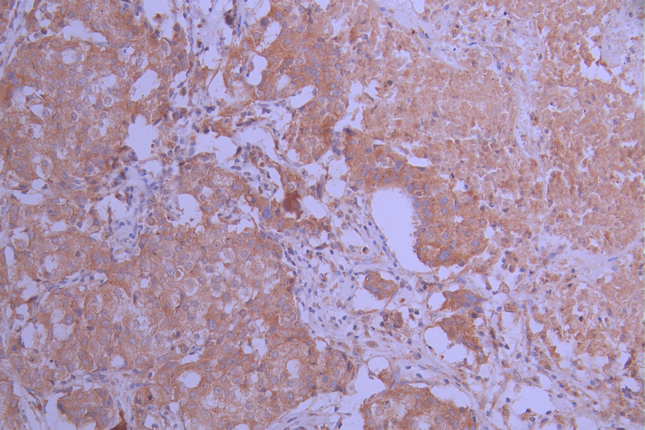

IHC image of CSB-RA292221A0HU diluted at 1:100 and staining in paraffin-embedded human breast cancer performed on a Leica BondTM system. After dewaxing and hydration, antigen retrieval was mediated by high pressure in a citrate buffer (pH 6.0). Section was blocked with 10% normal goat serum 30min at RT. Then primary antibody (1% BSA) was incubated at 4°C overnight. The primary is detected by a Goat anti-rabbit polymer IgG labeled by HRP and visualized using 0.05% DAB.

IHC image of CSB-RA292221A0HU diluted at 1:100 and staining in paraffin-embedded human pancreatic tissue performed on a Leica BondTM system. After dewaxing and hydration, antigen retrieval was mediated by high pressure in a citrate buffer (pH 6.0). Section was blocked with 10% normal goat serum 30min at RT. Then primary antibody (1% BSA) was incubated at 4°C overnight. The primary is detected by a Goat anti-rabbit polymer IgG labeled by HRP and visualized using 0.05% DAB.